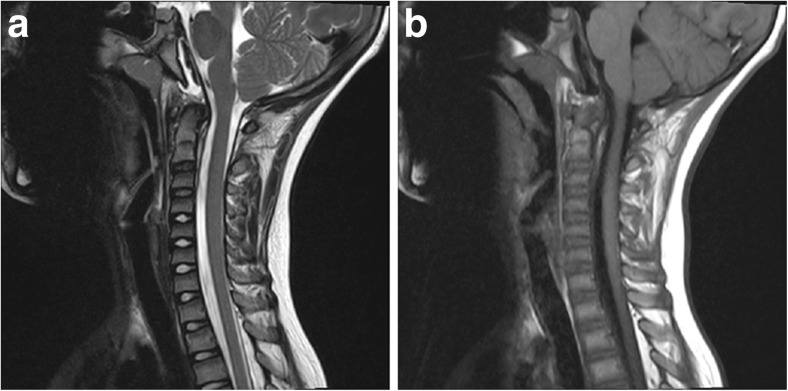

CT of the head revealed a hemorrhage along the dorsum sella, clivus, and dens (Fig. 1a, 1b). MRI brain and cervical spine were obtained to evaluate the hematoma and the craniocervical junction for signs of instability; the retroclival hematoma appeared in the subdural space and epidural space; there was T2 hyperintensity in atlanto-occipital joints and blood along the tectorial membrane (Fig. 2a, 2b). Subsequently, cervical spine flexion/extension x-rays were obtained, which demonstrated no instability and the cervical collar was discontinued. The patient had a prolonged hospitalization due to a duodenal hematoma and associated feeding issues. At discharge, 19 days after the accident, he exhibited intact eye movements.

Fig. 2.

a, b Sagittal T2 and T1 MR demonstrate rupture of tectorial membrane, with hematoma both ventral and dorsal to the membrane. Epidural hematoma tracks to mid-body of the dens, while subdural hematoma tracks to inferior C3 body

Retroclival subdural hematoma (rcSDH) has been reported less often than epidural hematoma (rcEDH). However, both can co-present, particularly in violent injuries [10]. Tables 1, 2, 3, and 4 summarize the available English literature. In the pediatric population, there have been 30 cases of rcEDH and 16 cases of rcSDH; in the adult population, there have been 8 cases of rcEDH and 21 cases of rcSDH. The tectorial membrane helps define the distinction between the epidural space and the subdural space, where the former is ventral to the membrane and the latter is dorsal to the membrane [11]. The tectorial membrane is the rostral continuation of the posterior longitudinal ligament, attached inferiorly to the posterior body of the axis and superiorly to the occipital bone along the clivus [11]. RcEDH are restricted by the boundaries of the membrane (that is, from the mid-portion of the clivus to the middle of the body of the axis); rcSDH are not restricted and can disseminate from the intracranial to the spinal subdural space [11]. The MRI (Fig. 2a, 2b) from our patient demonstrated stripping of the tectorial membrane, with focal areas of disruption; the ventral fluid collection tracking down to the mid body of the odontoid is consistent with an epidural hematoma; however, there is also a collection that exists posterior to the tectorial membrane and tracks more inferiorly to the posterior of the C3 body; this collection is consistent with a subdural collection.